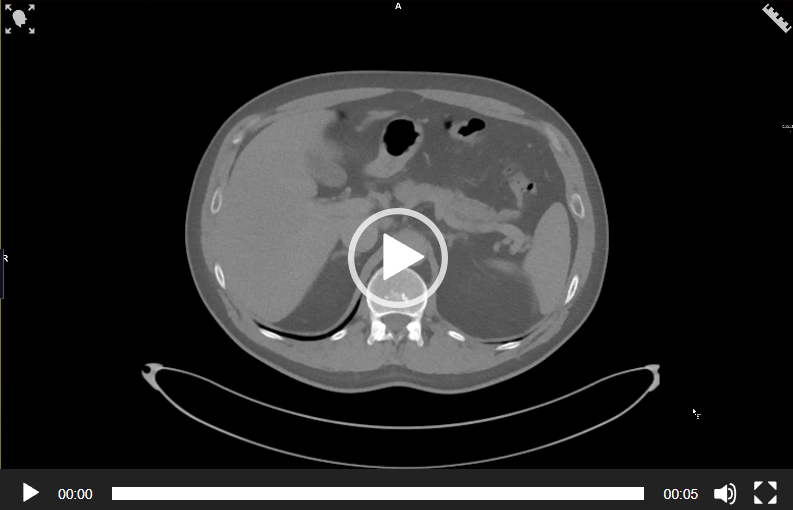

CAZ nr 7: uretero-hidronefroză dreaptă gradul II prin calcul inclavat în ureterul proximal complicată cu ruptură de căi urinare superioare

Video 1: reconstrucţie axială din examinare CT abdominală fără substanţă de contrast; se vizualizează un calcul millimetric parţial obstructiv în grupul caliceal superior drept şi uretero-hidronefroză dreaptă gradul II cu decalibrare la nivelul ureterului proximal la 4 cm de joncţiunea pielo-ureterală unde este prezent un calcul radioopac de 0.5 cm.